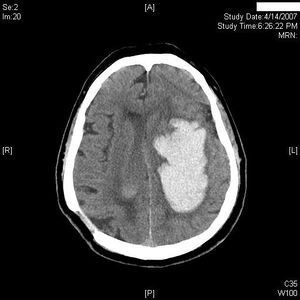

Left intraventricular hemorrhage and cerebral hematoma.

Management of IVH is primarily directed at controlling intracranial pressure through an external ventricular drain (EVD), but this catheter often becomes occluded by coagulated blood. The fibrinolytic system of the cerebrospinal fluid is limited, and blood may remain in the ventricles for months after a hemorrhage. IVH has a poor prognosis, partly because of the continuing mass effect of blood clots on the ventricular walls. Therefore, investigators have administered fibrinolytic agents directly into the ventricles of patients with IVH. Clinical studies of fibrinolytic therapy for IVH have found a 30 to 35% reduction in mortality with treatment, but have not yet clearly documented an improved neurologic outcome for the survivors.